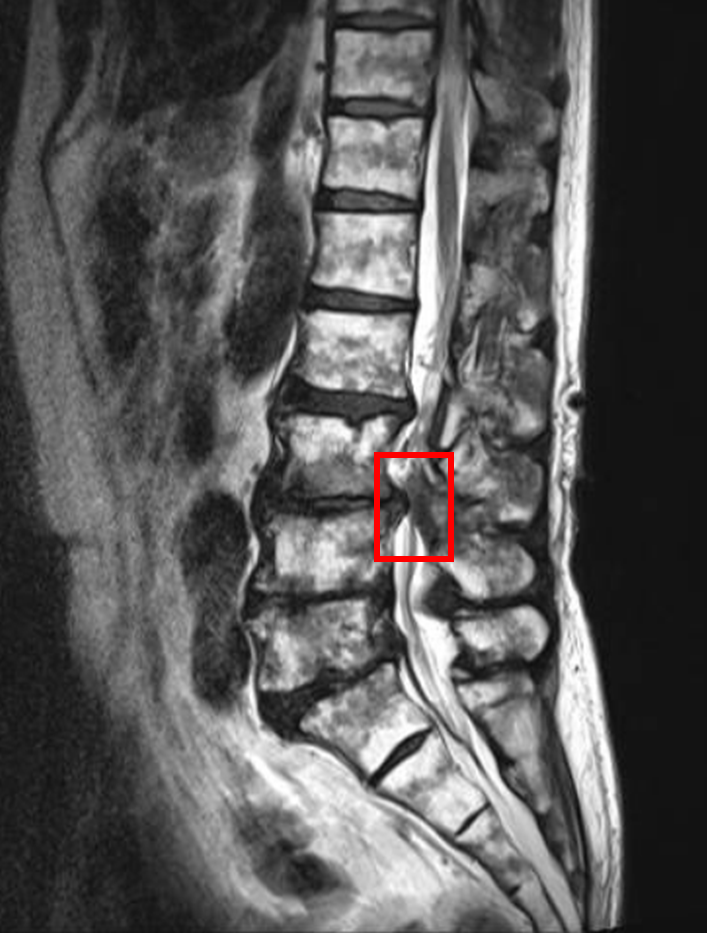

この患者様は赤い枠で示されている箇所(L3/4)に脊柱管狭窄症を認めます。